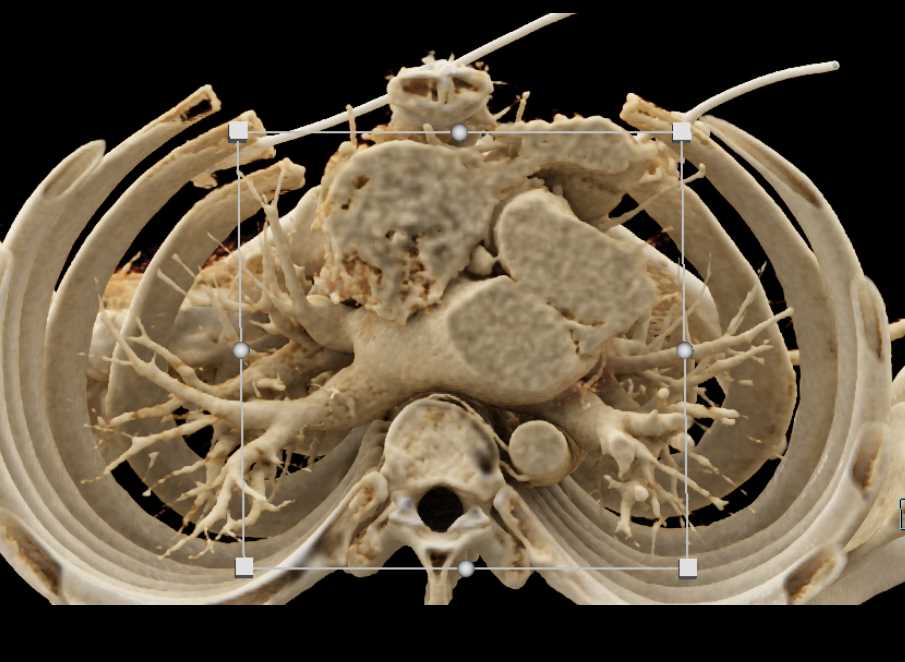

Aortic Valve Repair